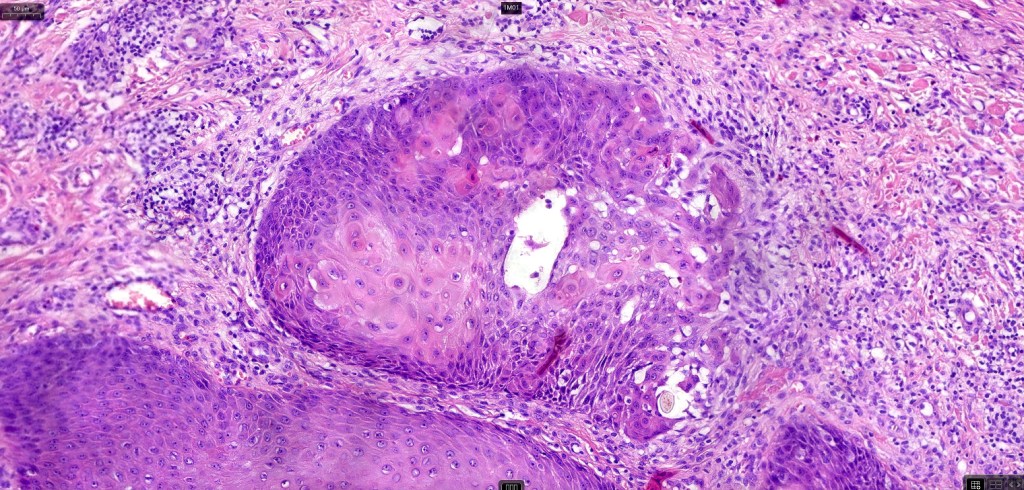

•Infundibular cyst lined by acanthotic squamous epithelium showing marked hypergranulosis, hyperkeratosis & parakeratosis

•Conspicuous, enlarged keratohyalin granules

•Koilocytosis

•Squamous eddies are often a prominent feature